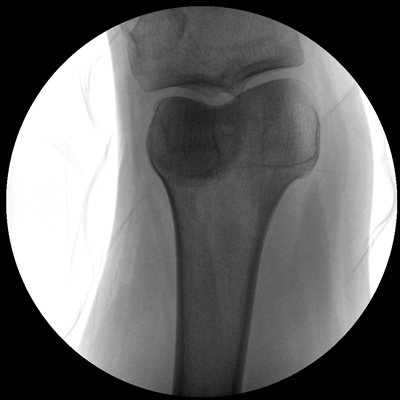

小巧輕便 超凡靈動(dòng) PLX C1116

●全數(shù)字化百萬像素影像系統(tǒng),圖像清晰